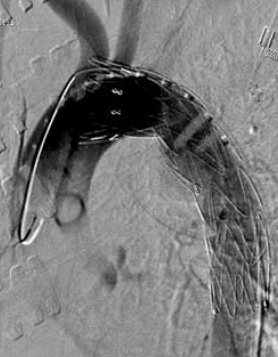

4. ábra.

4. sorszámú betegünk DSA felvétele az isthicus aorta III. stádiumú tompa aorta sérülését mutatja.

4. 22 éves fiatal ffi motorbaleset során szenvedett el mellkasi zúzódást, ami a típusos szakaszon álaneurysma képződéssel társult. A diagnózist mellkas röntgenfelvételek és DSA biztosította. Felkartörés rögzítést követően stabil morfológiai állapotban, 20 nappal a sérülés után stentgraft beültetést végeztünk subclavia transpositio nélkül (4.,5. ábra).

5. ábra.

A 4. ábrán mutatott eset megoldása stent graft beültetéssel.